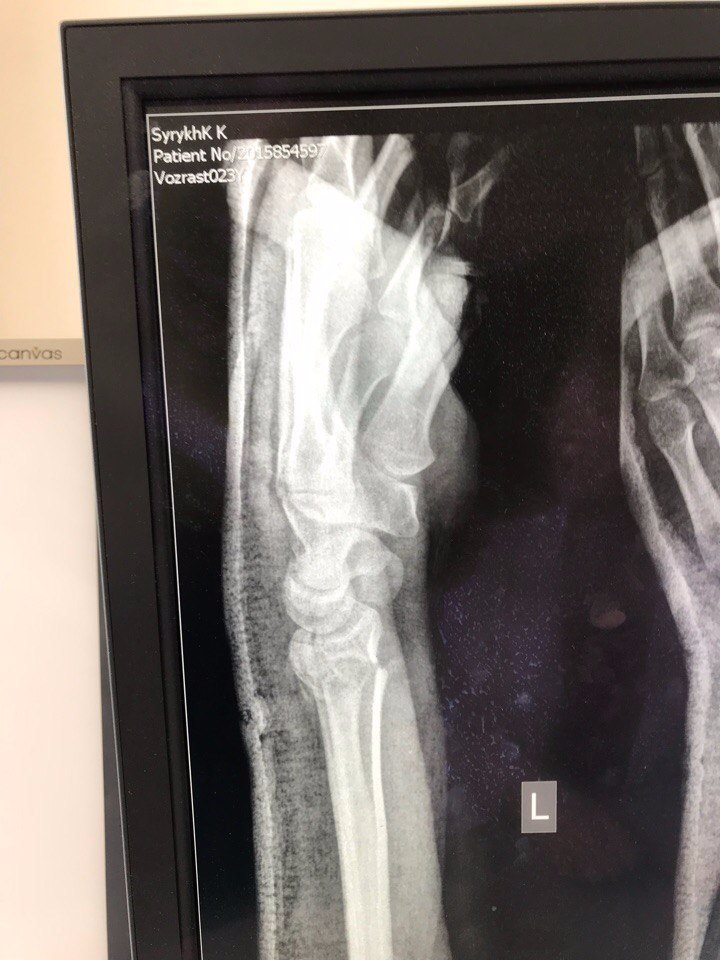

Надо сказать, что это было не самое жесткое падение. Костя в этот же день, сломает руку, но узнаем мы об этом только в Воронеже, когда ее надо будет повторно ломать, а пока веселимся и шнуруем этому биг бро боты.